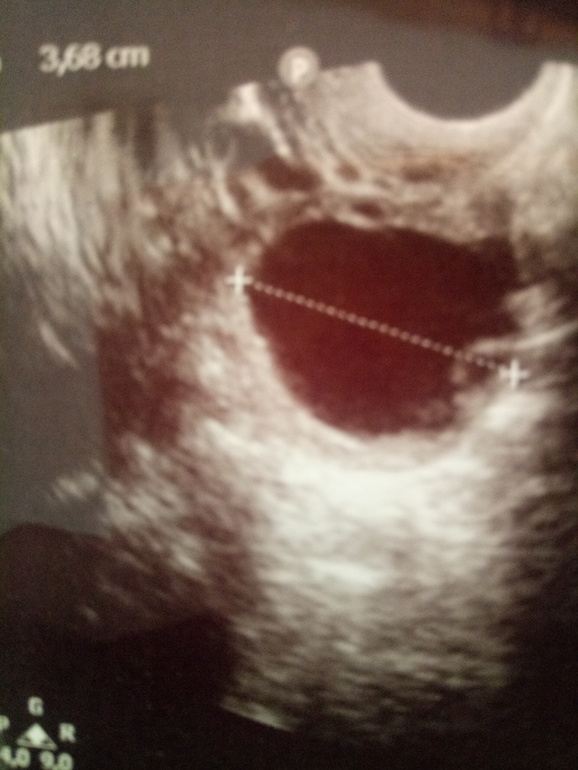

ФолликулометрияС 23.02 по 02.03 были кд, немного дольше обычного. Ровно через неделю началась какая-то мазня, плавно переходящая в кд. Все бы ничего, но ко всей этой радости прибавились боли в левом яичнике, редкие, но ощутимые. На 4 день страданий решила сходить на узи-фоликулярная киста ЛЯ😦